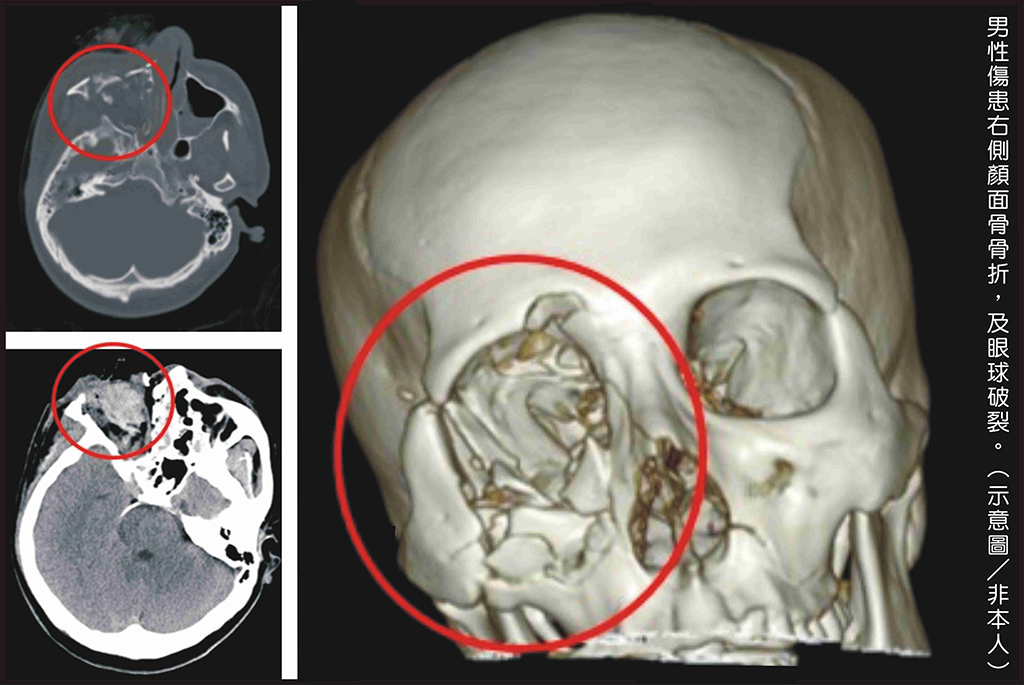

黃勉書醫師表示,男性傷患經檢查顯示嚴重的燒燙傷,右側顏面骨爆裂性骨折、頭骨破裂,合併右眼球破裂。

男性傷患右側顏面骨骨折及眼球破裂。(示意圖/非本人)

日前一名男性,因好奇而把玩鞭炮,輕忽鞭炮爆炸的威力,結果造成永久性無法回復的傷害。當時病人到院時右側臉部血肉模糊,伴隨不斷的哀號。檢查顯示嚴重的燒燙傷而且右側顏面骨爆裂性骨折,頭骨破裂,合併右眼球破裂。彰基醫學中心急診團隊緊急搶救,並匯集眼科、整形外科、神經外科醫師做後續照護,還好病人順利保住性命、意識清楚,穩定治療,後續仍有漫長復原之路。

彰基外傷科主任黃勉書醫師表示,逢年過節大家難免會施放鞭炮,在施放鞭炮的過程要小心並注意安全。這個個案在玩鞭炮時不小心炸傷了眼睛,造成右眼球破裂,顏面部嚴重的燒燙傷,顏面骨開放式骨折,送至彰化基督教醫院第一時間先保護呼吸道,再轉送至手術房進行眼球的摘除術,以及清創並縫合傷口。